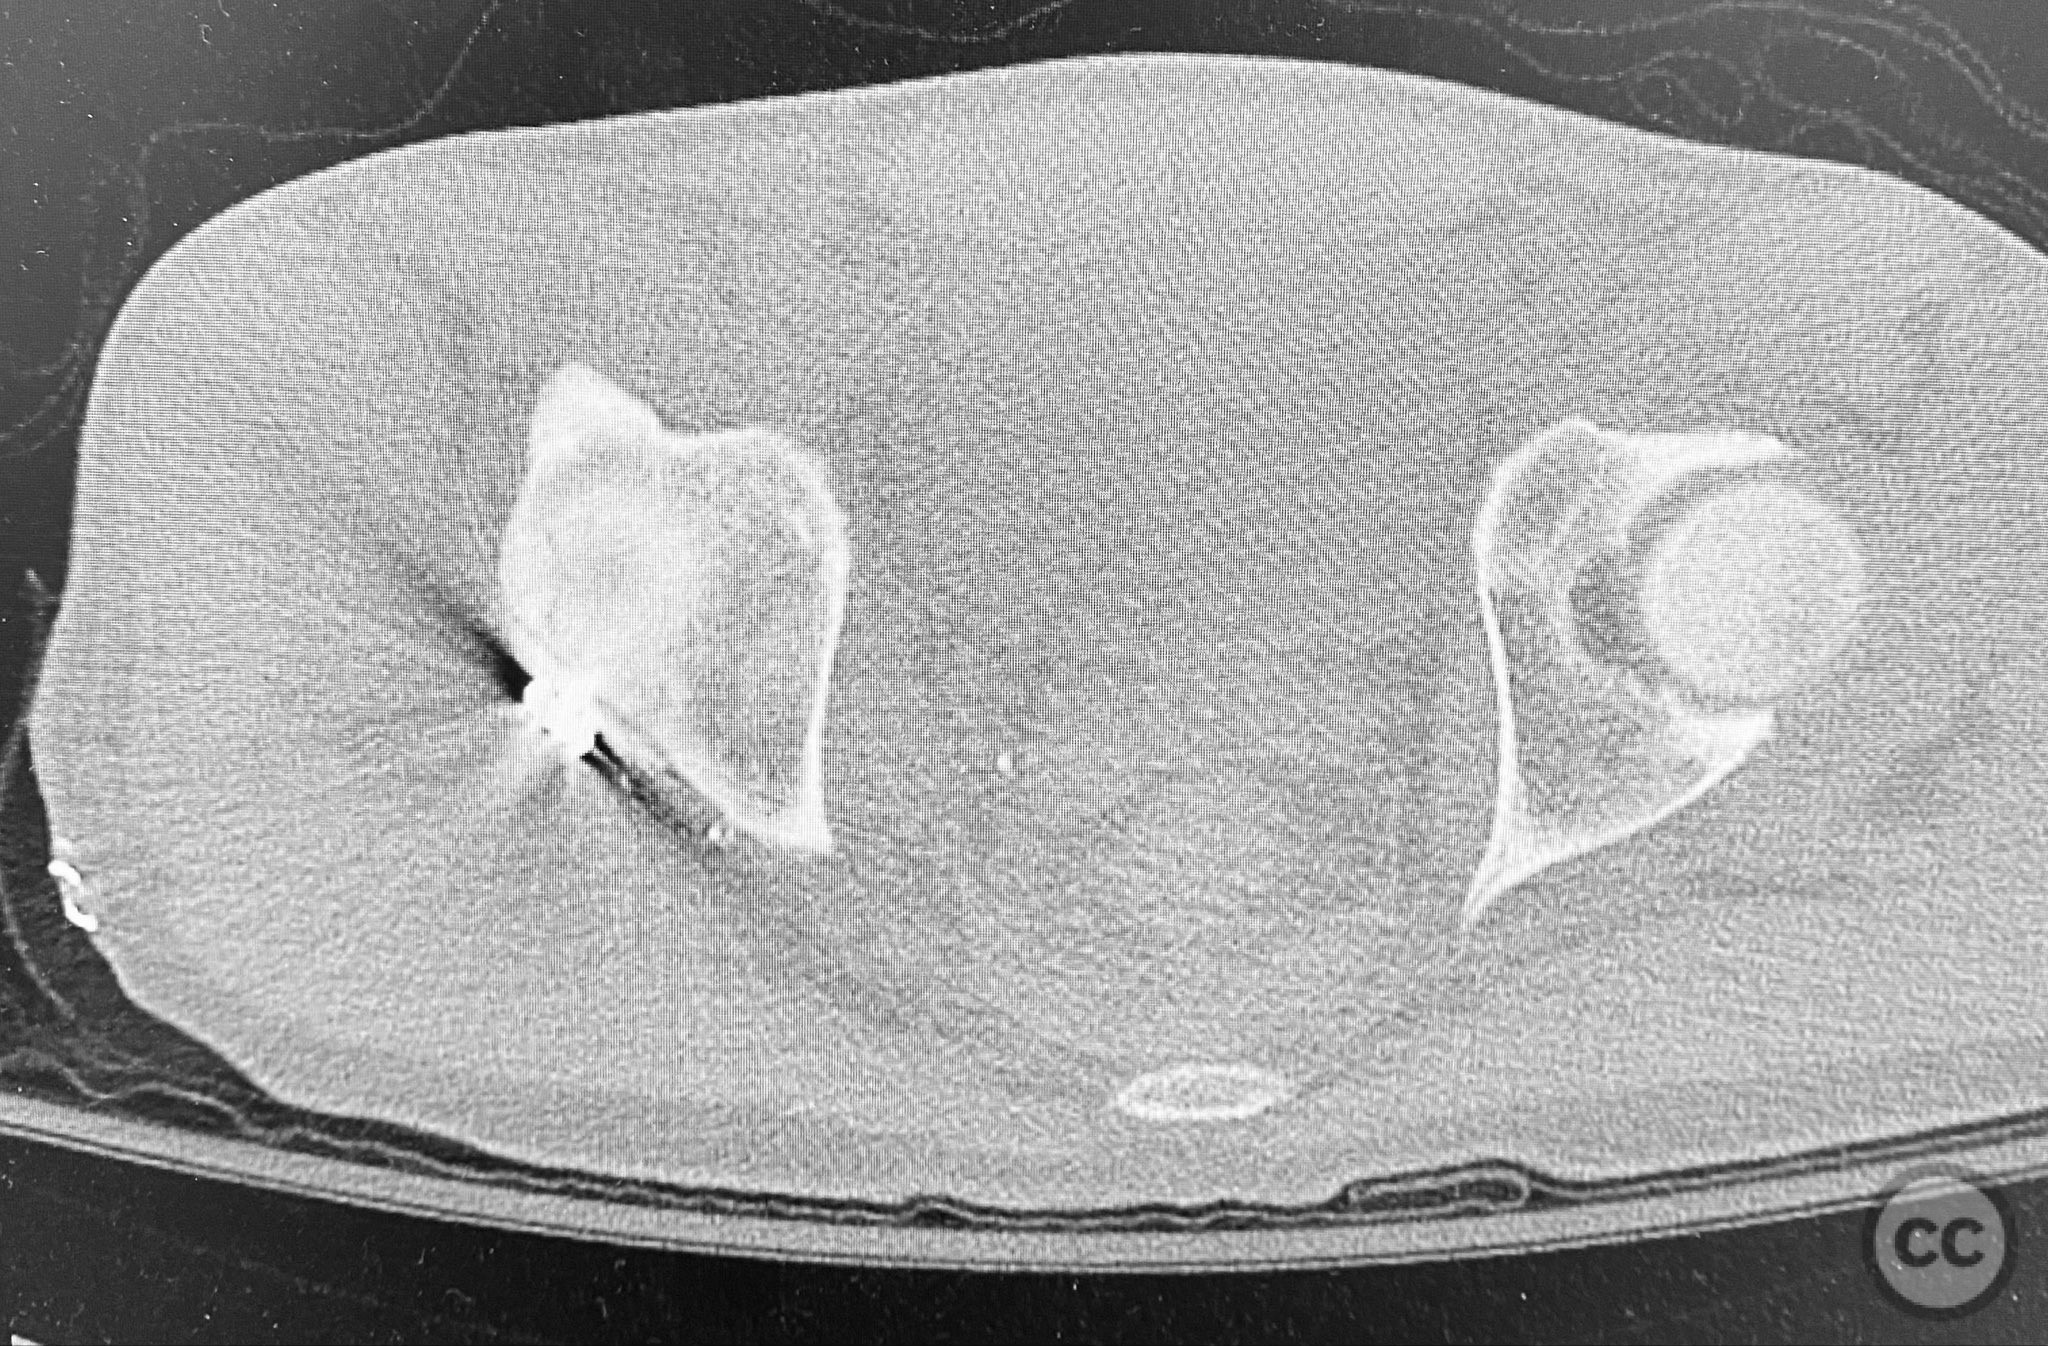

Planning remarks:  The preoperative plan included advanced imaging with CT, including 3D surface renderings, to further delineate the extent of articular impaction, wall fragment size, and comminution. The plan was for open reduction and internal fixation via a posterior Kocher-Langenbeck approach in the prone position. Elevation of impacted articular segments was planned, with structural support using autologous bone graft harvested from the greater trochanter. Fragment-specific fixation was planned with a spring hook plate for the cranial wall fragment and a reconstruction plate for the main posterior wall fragment.

The initial failed closed reduction likely resulted from interposed soft tissue or bony fragments, or inadequate sedation/muscle relaxation. Repeat reduction under improved conditions was successful prior to definitive fixation. 3D CT renderings provided enhanced visualization of impaction zones and comminution, facilitating preoperative planning for grafting and fragment-specific fixation. Intraoperatively, elevation of the impacted dome required careful manipulation to avoid further chondral injury. Use of a spring hook plate provided secure fixation of the cranial wall fragment, while the reconstruction plate supported the main wall fragment. Postoperative CT confirmed satisfactory reduction and implant positioning.